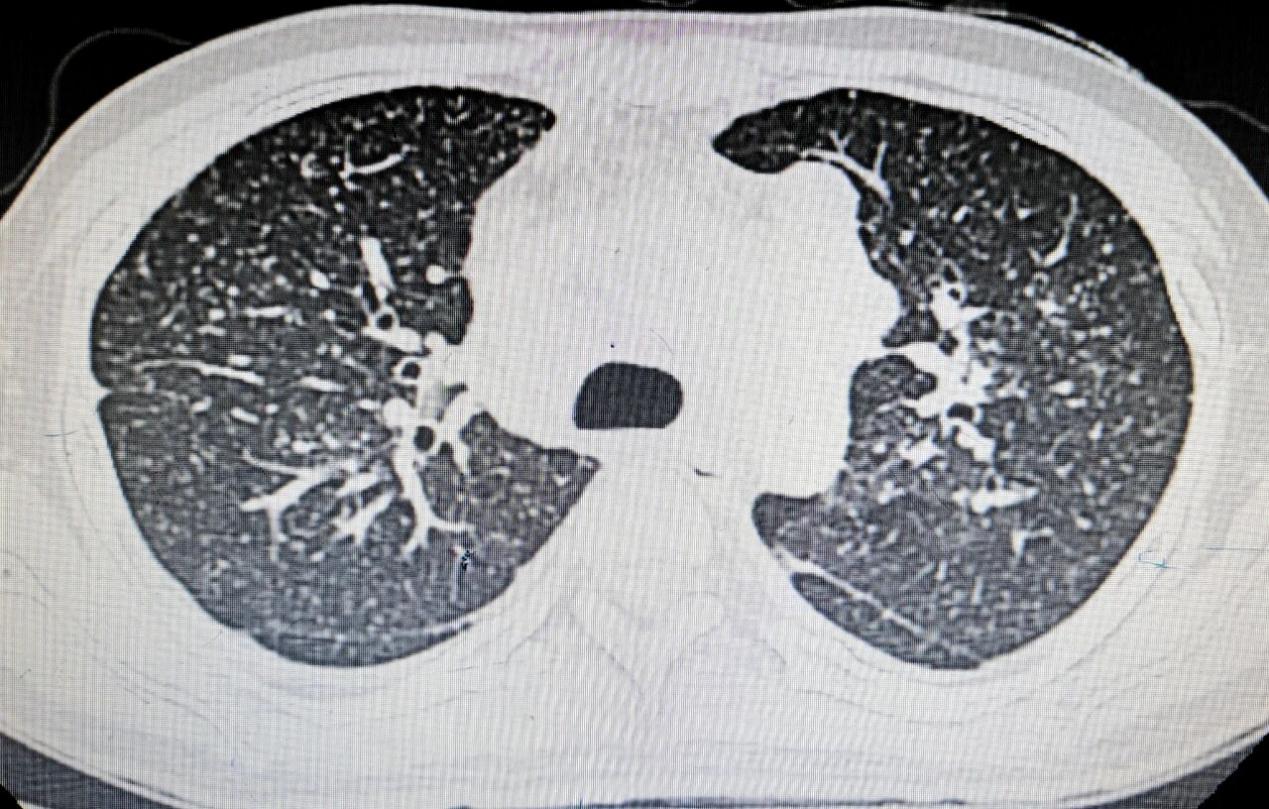

阳光讯(记者 郑亚雷 通讯员 杨莹)对于 30 岁的孙先生(化名)而言,一场突如其来的重病,将他无情地推到了生死边缘。原本处于而立之年的他,在反复咳嗽、发热 20 多天后,被确诊为“粟粒样肺结核”。紧接着,高烧不退、血压骤降,迅速陷入“脓毒性休克”,生命体征极不稳定,重度感染如影随形,多个器官面临衰竭风险,每一秒都可能是他与世界的最后告别。